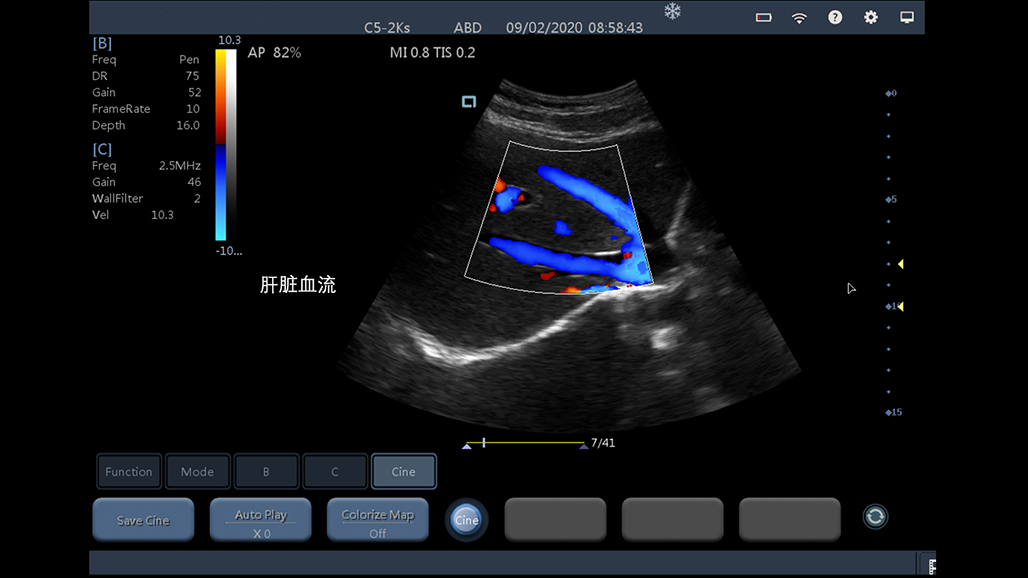

Multi-Mode

多模式支持

• 大凸

腹部

肾脏

妇科产科

心脏

肺等